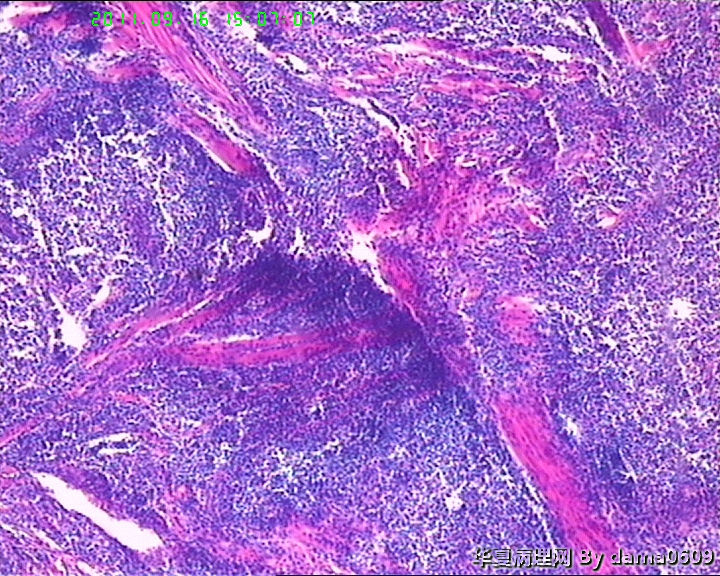

• 背部肿物,急请老师看看!!图3

图3